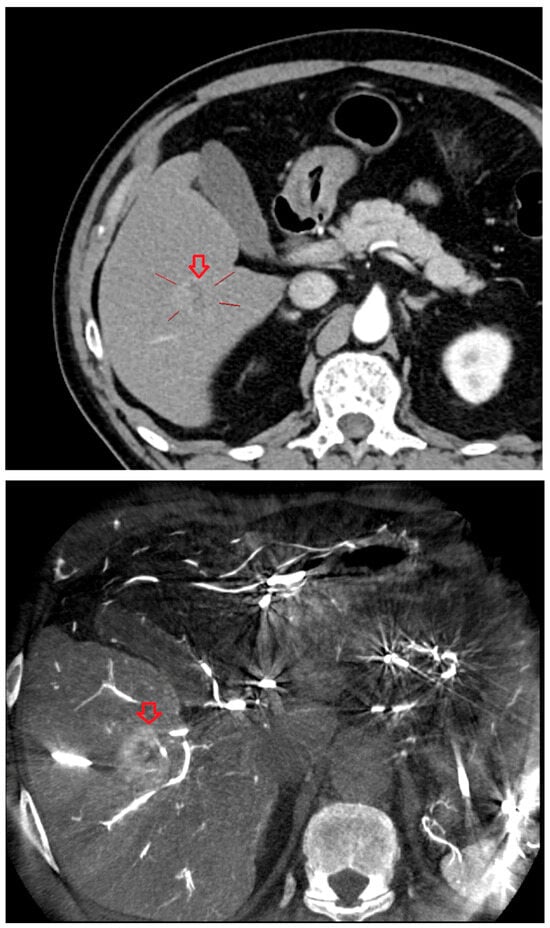

As shown in Figure 1, angio-CBCT allows for higher visibility of the target mass, as reflected in the ΔHU values. This can be visually confirmed in several cases. Representative cases in Figure 2 and Figure 3 demonstrate how the target mass is much more conspicuous to the operator on angio-CBCT compared to pre-procedural CT. In Figure 4, a mass, which was nearly invisible on pre-procedural CT, was identified through angio-CBCT, aiding the targeting process. Figure 5 shows a case where a mass with discordance between USG and CEUS was confirmed using angio-CBCT, leading to needle repositioning and achieving complete ablation. Finally, Figure 6 illustrates a case where a residual tumor was identified on angio-CBCT and re-ablation resulted in complete ablation.

Figure 2. CT images from a patient with hepatocellular carcinoma undergoing angio CBCT-guided RFA. (Top): pre-procedural CT (portal venous phase; lesion 128.7 HU, red arrow = HCC mass). (Bottom): intraprocedural angio CBCT (lesion 1499.7 HU, red arrow with star = HCC mass). ΔHU = 1298.0 HU. (intra lesion − intra background) − (pre lesion − pre background).